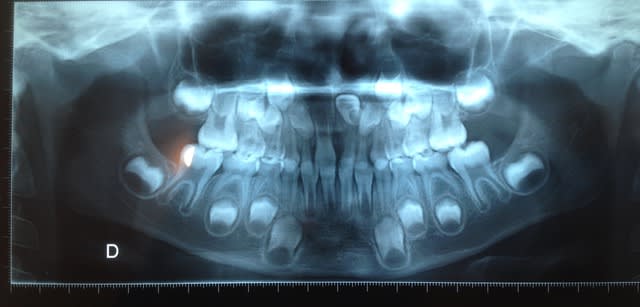

un jeune enfant de 7.5 ans , absence de mise en place de la 21 après examen radiologique on note une mal position sévère.

la 61 est nécrosé depuis qq temps avec kyste ce qui explique le mouvement de la dent; la lésion évoluant au niveau de la face palatine de la couronne de 21 a crée cette rotation.

1 avulsion de 61 rapide, qui va te confirmer le lésion apicale

2 mainteneur espace

3 trois mois plus tard si pas de début de normalisation, chirurgie bouton et tractation

Une fois la 61 retirée pas de curetage particulier à cette age la on voit des miracles

Vérifier aussi 62

L asymétrie 51/61 est typique de ce genre de problème.